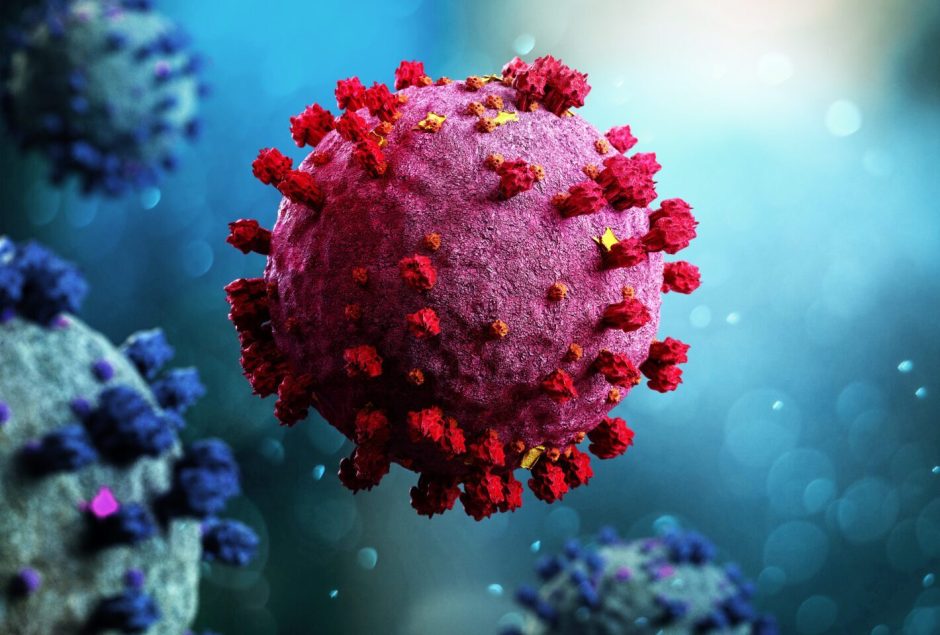

La covid augmenterait tout de suite le risque de troubles cardiaques et du diabète de type 1